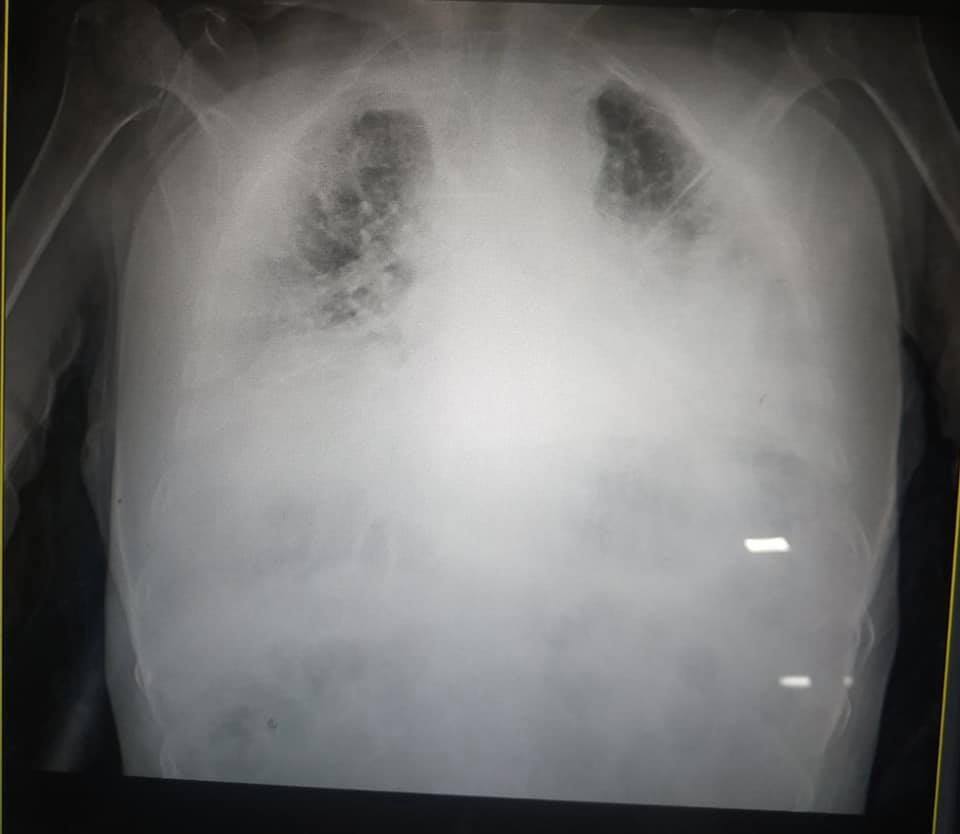

Украинская журналистка Ирина Заславец показала фото рентгена легких, пораженных коронавирусной болезнью (COVID-19).

Снимки она опубликовала в Facebook после общения с главой реанимации Клинической больницы скорой медицинской помощи Львова Натальей Матолинец.

"Это одни из самых страшных легких, которые я видела в жизни", – отметила врач.

Заславец добавила, что ранее из Винников в областную больницу доставили 18 пациентов с COVID-19, 7 из них – в реанимации. Все в критическом состоянии, подчеркнула журналист.